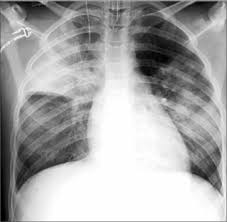

This lung infection produces coughing, fever, shortness of breath, and chest pain. Bacterial pneumonia is characterized by exudative solidification (consolidation) of the pulmonary tissue, which is caused by bacterial invasion of the lung parenchyma. Learn about causes, risk factors, prevention, signs and symptoms. Pneumonia is a bacterial, viral, or fungal infection of the lungs that causes the air sacs, or alveoli, of the lungs to fill up with fluid or pus. Pneumonia por pneumocystis jirovecii 4.

Abcesso pulmonar (temos observado muitos casos de abcessos. A pneumonia eosinoffii~a aguda (pea) e uma doe~ rara, de etiologia desconhecida, caracterizada por eosinofilia pulmonar marcada, geralmente niio associada a aumento dos eosinofilos no sangue. Bacterial pneumonia is an infection of your lungs caused by certain bacteria. Bacterial pneumonia is a type of pneumonia caused by bacterial infection. When pneumonia is caused by streptococcus pneumoniae, mycoplasma pneumoniae, or other bacteria, it's called bacterial pneumonia. Pneumonia poate fi cauzată și de inhalarea secrețiilor de vomă sau a unor substanțe. Clinical presentation bacterial pneumonia has symptoms similar to other pneumonia. Bacterial pneumonia is characterized by exudative solidification (consolidation) of the pulmonary tissue, which is caused by bacterial invasion of the lung parenchyma. Histologic features and clinical significance. This lung infection produces coughing, fever, shortness of breath, and chest pain. Learn about bacterial pneumonia causes, symptoms, the contagious period, treatments, and recovery time. Pneumonia can be generally defined as an infection of the lung parenchyma, in which consolidation of the sections bacterial pneumonia. Streptococcus pneumoniae (j13) is the most common bacterial cause of pneumonia in all age groups except.